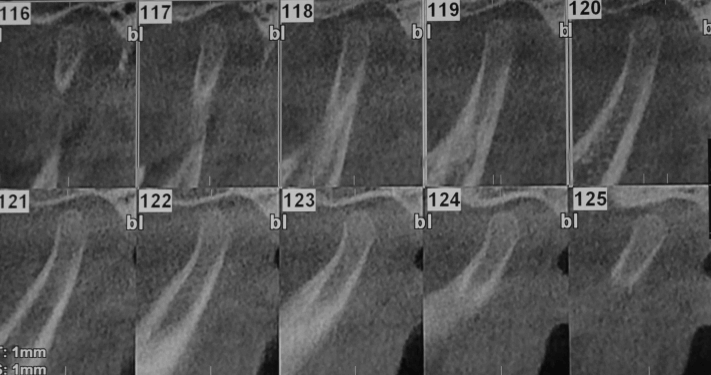

Tomografía Cone Beam Inicial

Evidencia tomográfica de la rápida evolución de la hiperplasia condilar